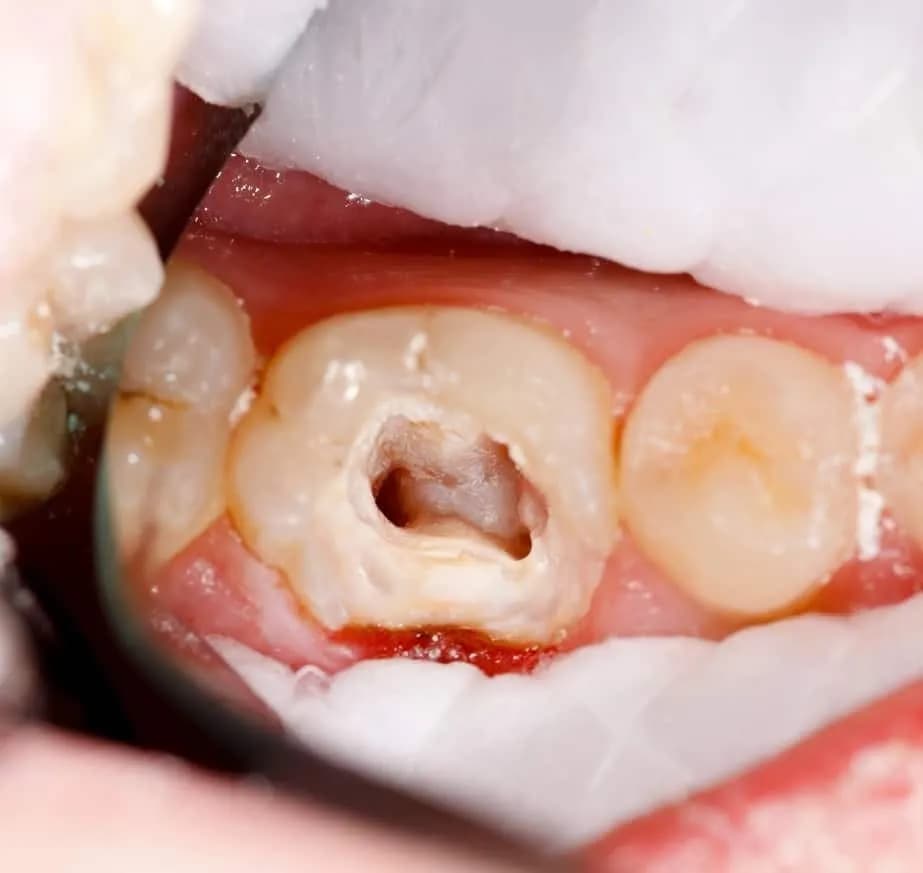

Istnieje kilka czynników, które mogą prowadzić do zwiększenia liczby kanałów w zębie 6. Na przykład, pewne warunki dentystyczne, takie jak próchnica czy zapalenie miazgi, mogą wpływać na rozwój dodatkowych kanałów. W przypadku zębów z dużymi ubytkami, organizm może wytwarzać dodatkowe kanały w odpowiedzi na uszkodzenia. Dodatkowo, złożoność budowy anatomicznej zębów trzonowych również może prowadzić do większej liczby kanałów.

- Próchnica - może prowadzić do powstawania nowych kanałów w odpowiedzi na uszkodzenia.

- Zapalenie miazgi - może stymulować rozwój dodatkowych kanałów.

Leczenie kanałowe w zębie 6 jest niezwykle ważne, ponieważ ten ząb odgrywa kluczową rolę w procesie żucia. Złożona budowa kanałów w zębie 6 sprawia, że leczenie może być trudne i czasochłonne. Właściwe zrozumienie struktury kanałów jest kluczowe dla skuteczności terapii, ponieważ niewłaściwe leczenie może prowadzić do powikłań. Dlatego specjaliści zalecają przeprowadzanie leczenia pod mikroskopem, co pozwala na większą precyzję i dokładność.

Warto również zaznaczyć, że ząb 6 często jest narażony na problemy, takie jak próchnica czy zapalenie miazgi, co może zwiększać potrzebę leczenia kanałowego. Zrozumienie wyzwań związanych z tym procesem jest kluczowe dla pacjentów oraz dentystów, aby zapewnić jak najlepsze wyniki leczenia. Dzięki nowoczesnym technikom i narzędziom, można skuteczniej diagnozować i leczyć problemy związane z zębem 6, co przekłada się na lepsze zdrowie jamy ustnej.

Leczenie kanałowe w zębie 6 jest trudne z kilku powodów. Po pierwsze, ząb ten ma złożoną strukturę kanałów, co utrudnia ich dokładne oczyszczenie. Po drugie, ząb 6 często występuje w obszarze, gdzie sąsiaduje z innymi zębami, co może utrudniać dostęp do kanałów. Dodatkowo, zmiany patologiczne, takie jak zapalenie miazgi, mogą sprawić, że kanały będą bardziej wrażliwe i trudniejsze do leczenia. Wreszcie, różnice anatomiczne między pacjentami mogą prowadzić do nieprzewidywalnych trudności w trakcie procedury.